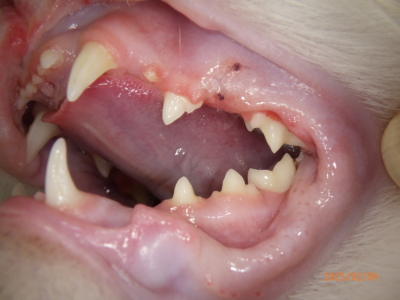

当院にて初診時、お口を確認するとまず、歯肉が赤くモリモリしていることがわかります。そして、奥の方は赤く腫れていないので、幸い口内炎にはなっていないようです(口内炎は喉のほうまで赤く腫れます)。歯は確かに本数は多いのですが、乳歯にしてはそれぞれの歯がしっかりしています。これらのことから、若齢猫の歯肉増殖症と、過剰歯の存在と推測しました。これらの病態の説明は後述しますが、いずれにしろ肉眼のみでの検査では診断も難しいため、全身麻酔下での歯科レントゲンを用いた精査、また歯肉の盛り上がった部位は一部採取して病理検査に提出することにしました。

当日の肉眼写真です。

参考としてほぼ正常な猫の歯はこんな感じです。歯並びと歯の数、歯肉の腫れ方が違います。